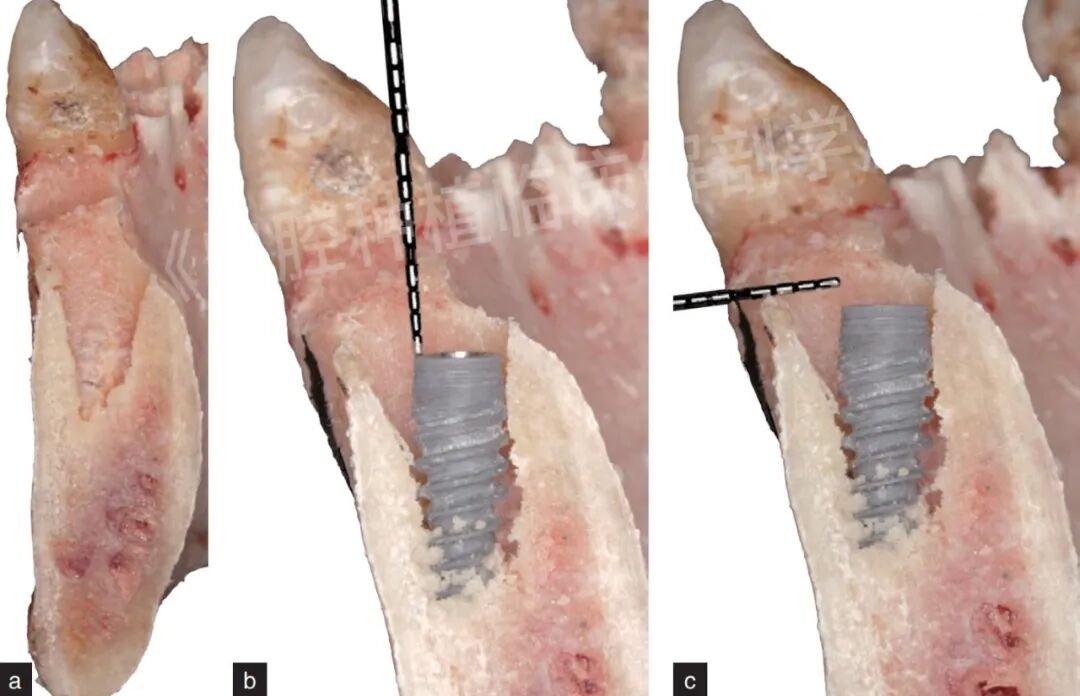

图8 左上中切牙即刻种植后种植窝。a为剖面图;b我种植体植入深度≥2 mm;c为种植体颈部与唇侧骨板的距离≥2 mm

图16 左下中切牙即刻种植后种植窝。a为剖面图;b为种植体植入深度≥2 mm;c为种植体颈部与唇侧骨板的距离≥2 mm